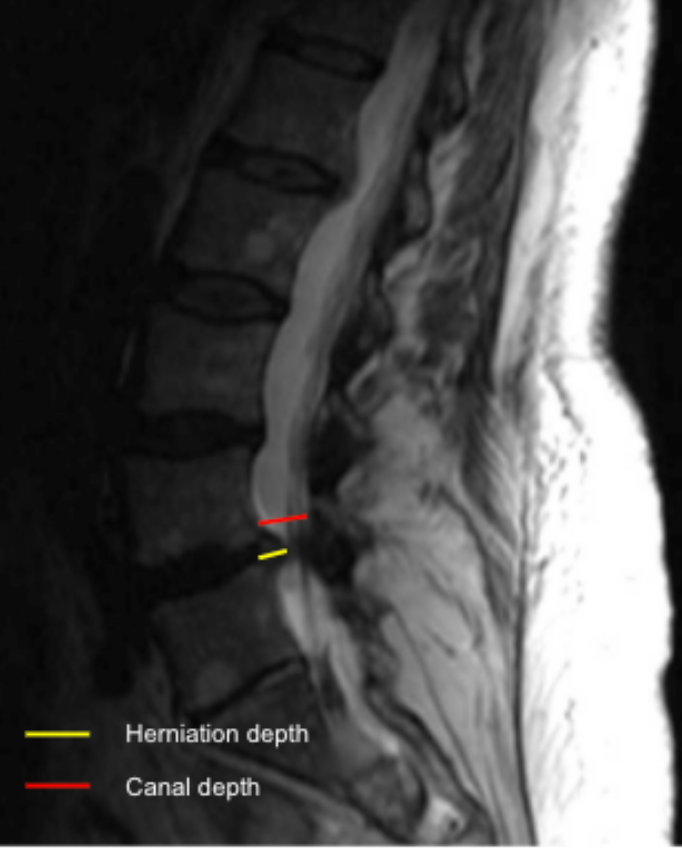

Disc herniation size quantifies the degree of posterior disc displacement beyond the normal vertebral body margin and expresses the extent of neural element encroachment. It can be reported as:

• Absolute protrusion depth (mm), or

• Relative size (%), calculated as a ratio of herniation depth to the anteroposterior diameter of the spinal canal at the same level.

• Draw a reference line along the posterior margin of the adjacent vertebral bodies (baseline).

• Measure the maximum herniation depth (HD):

• Draw a perpendicular line from the baseline to the most posterior point of the herniated disc material (mm).

• Measure the AP spinal canal diameter (CD) at the same level.

• Calculate relative herniation size (%):

Relative Size = HD/CD*100